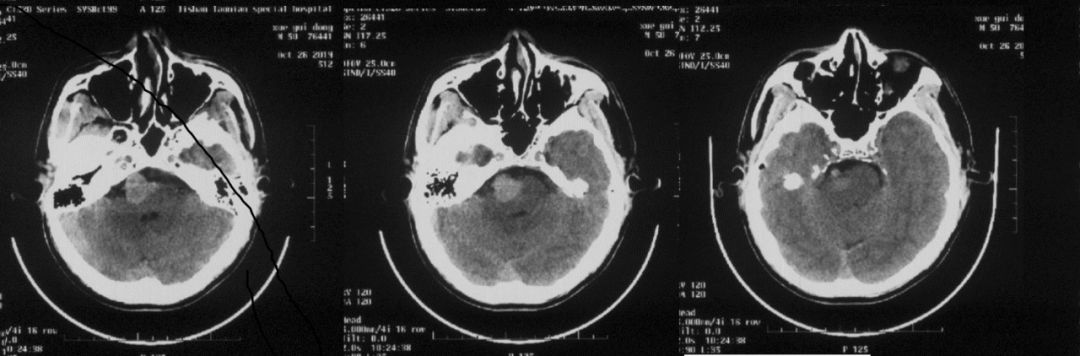

头颅CT:脑干周围高密度影,考虑血管瘤。

图1 头颅CT